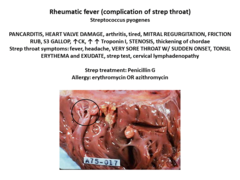

fever, headache, VERY SORE THROAT W/ SUDDEN ONSET, TONSIL ERYTHEMA and …

sudden onset of fever headache myalgia vomiting sore throat sore …